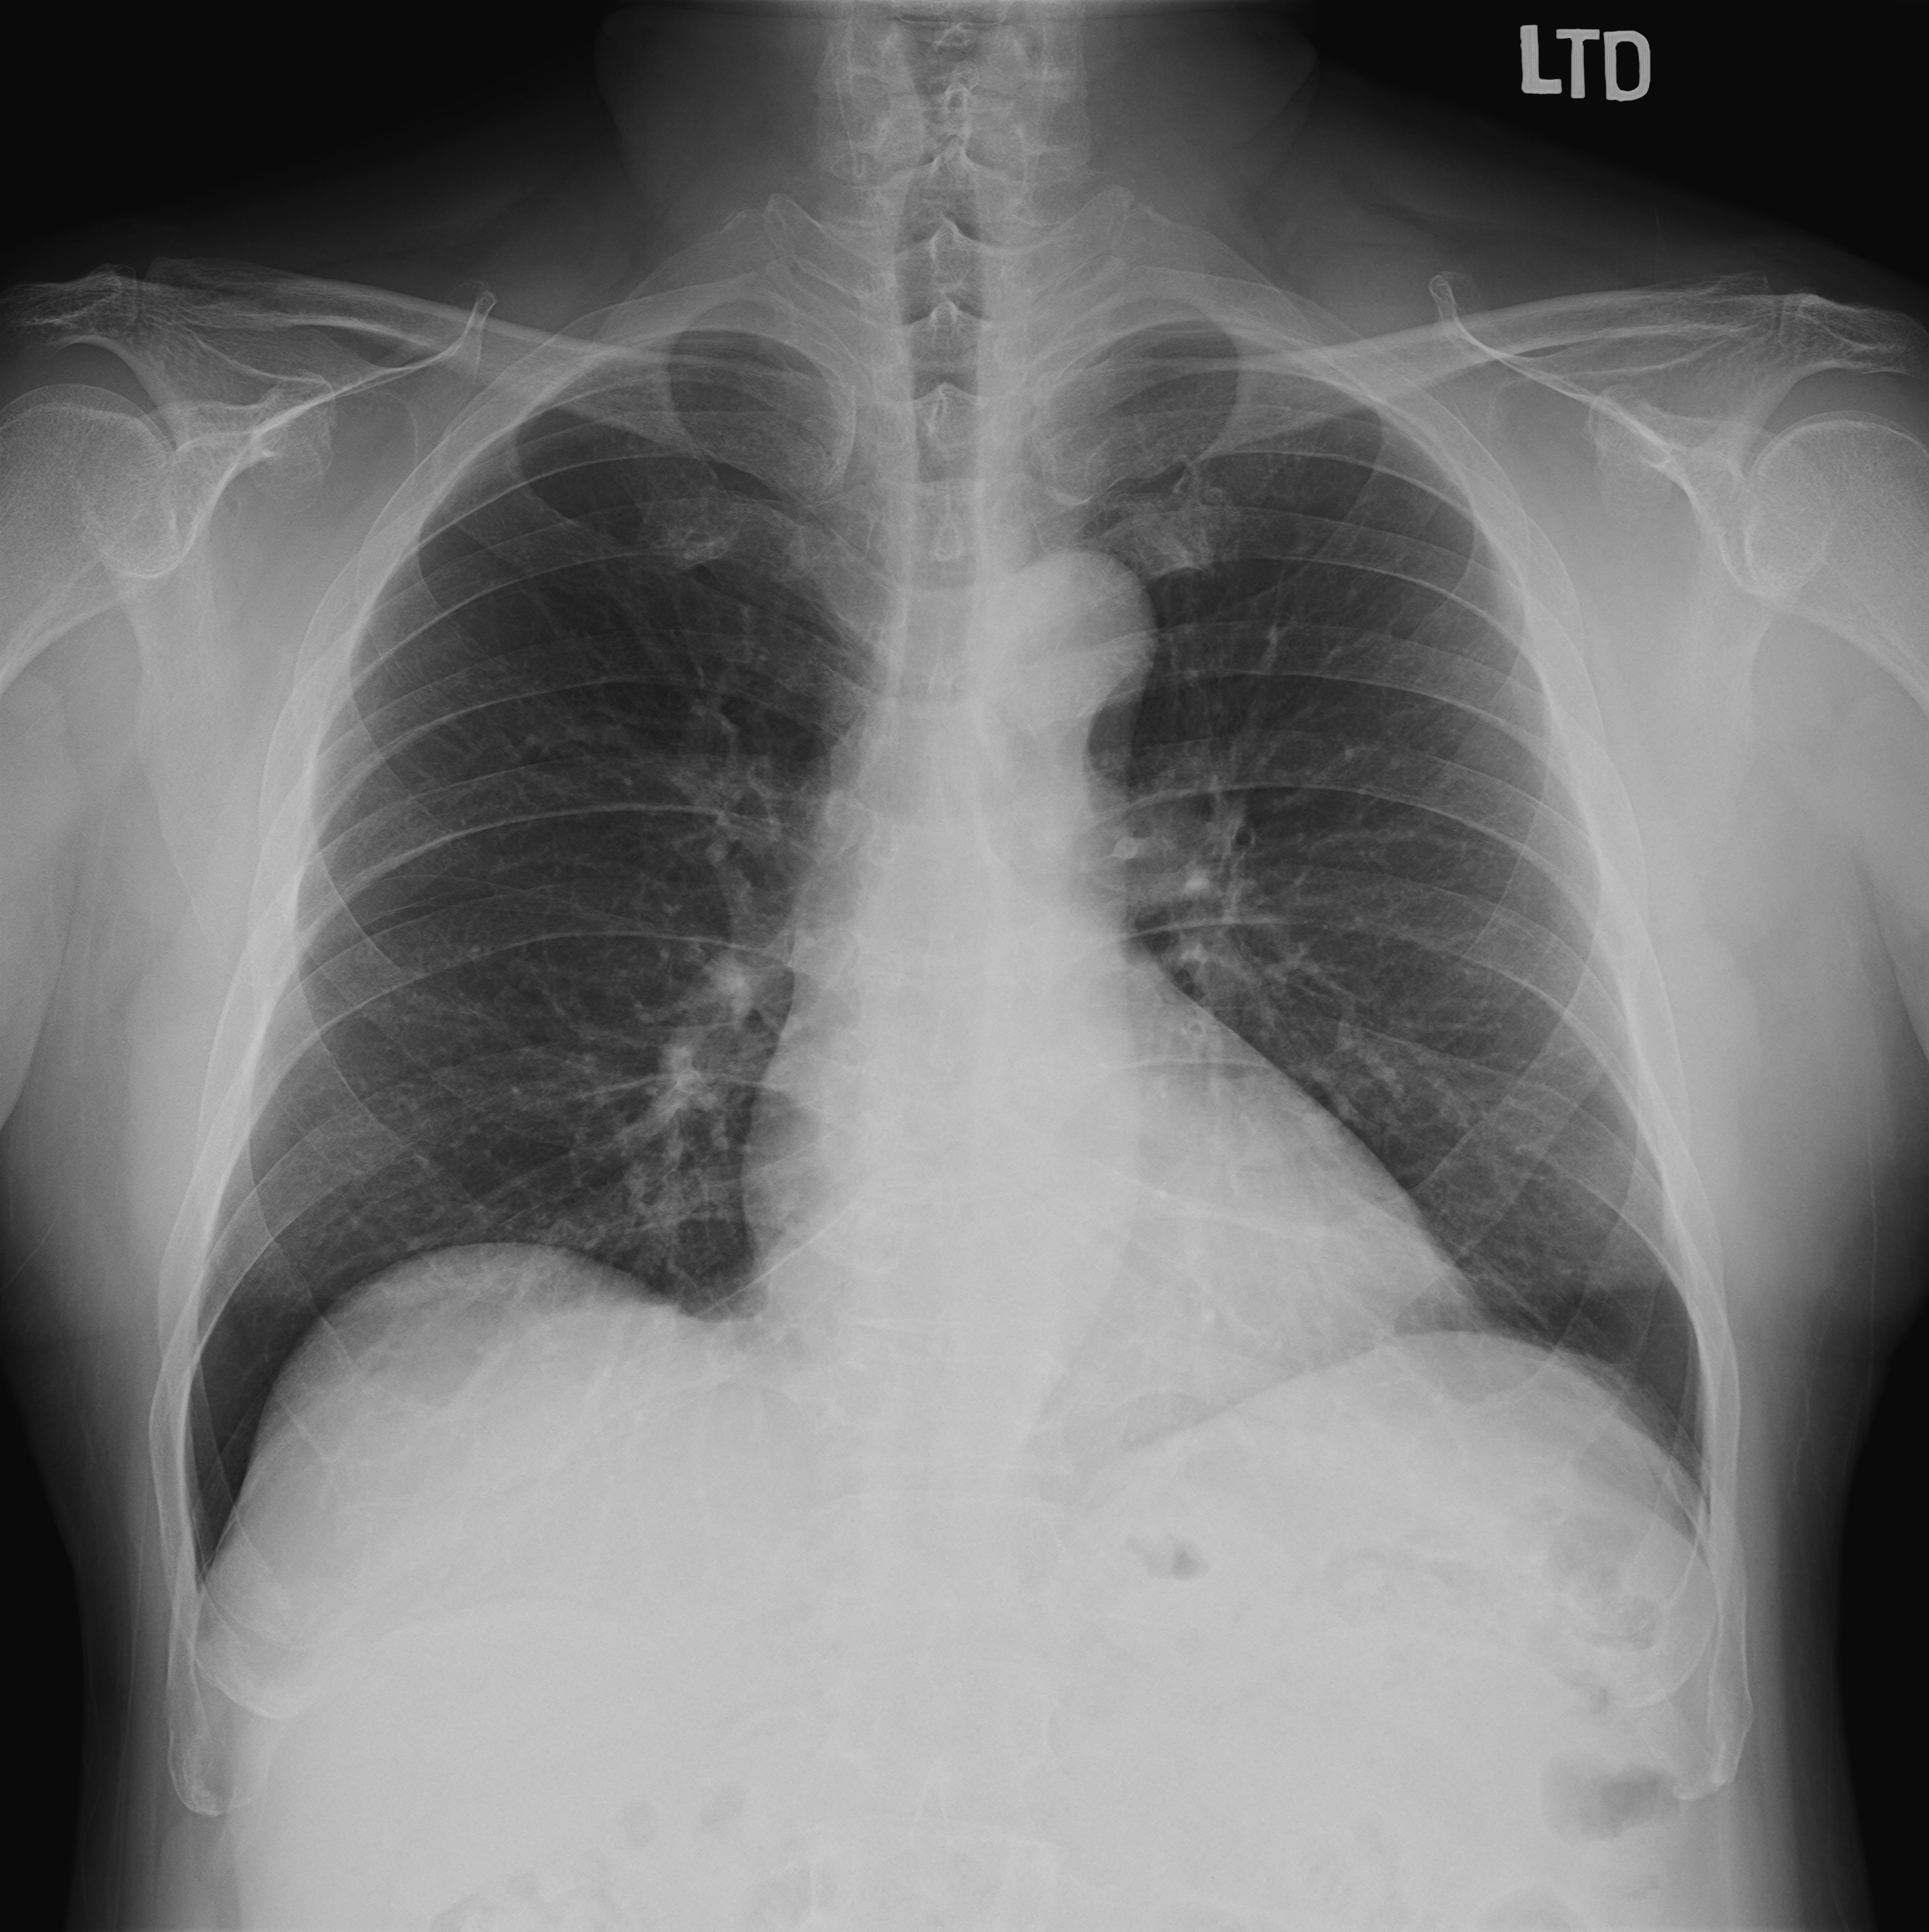

Treadmill's exercise ECG was performed, and showed ST depression over inferior and lateral leads. The exam was terminated before 90% predicted heart rate achieved(Bruce stage 2) due to dyspnea and the patient cannot follow up. Echocardiogram was also arranged, and showed mild AR, TR, mild to moderate MR and normal LV systolic wall motion with LVEF 55%. Chest X ray found no definite evidence of significant active lung lesion or cardiomegaly.